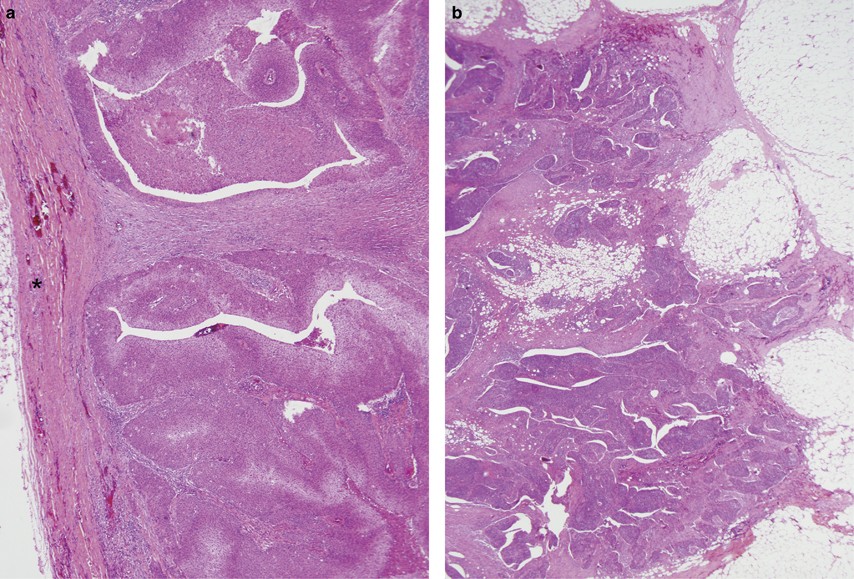

Figure 2

Extracapsular extension histologic features. (a) Grade 1 with tumor expanding the lymph node but confined by a thick capsule/pseudocapsule (designated by *), with which it has a smooth interface. (b) Grade 4 (or ‘soft tissue metastasis’) with tumor growing extensively and irregularly into adipose tissue without residual lymph node identifiable. (Hematoxylin and eosin staining; a=40 × magnification; b=20 × magnification).